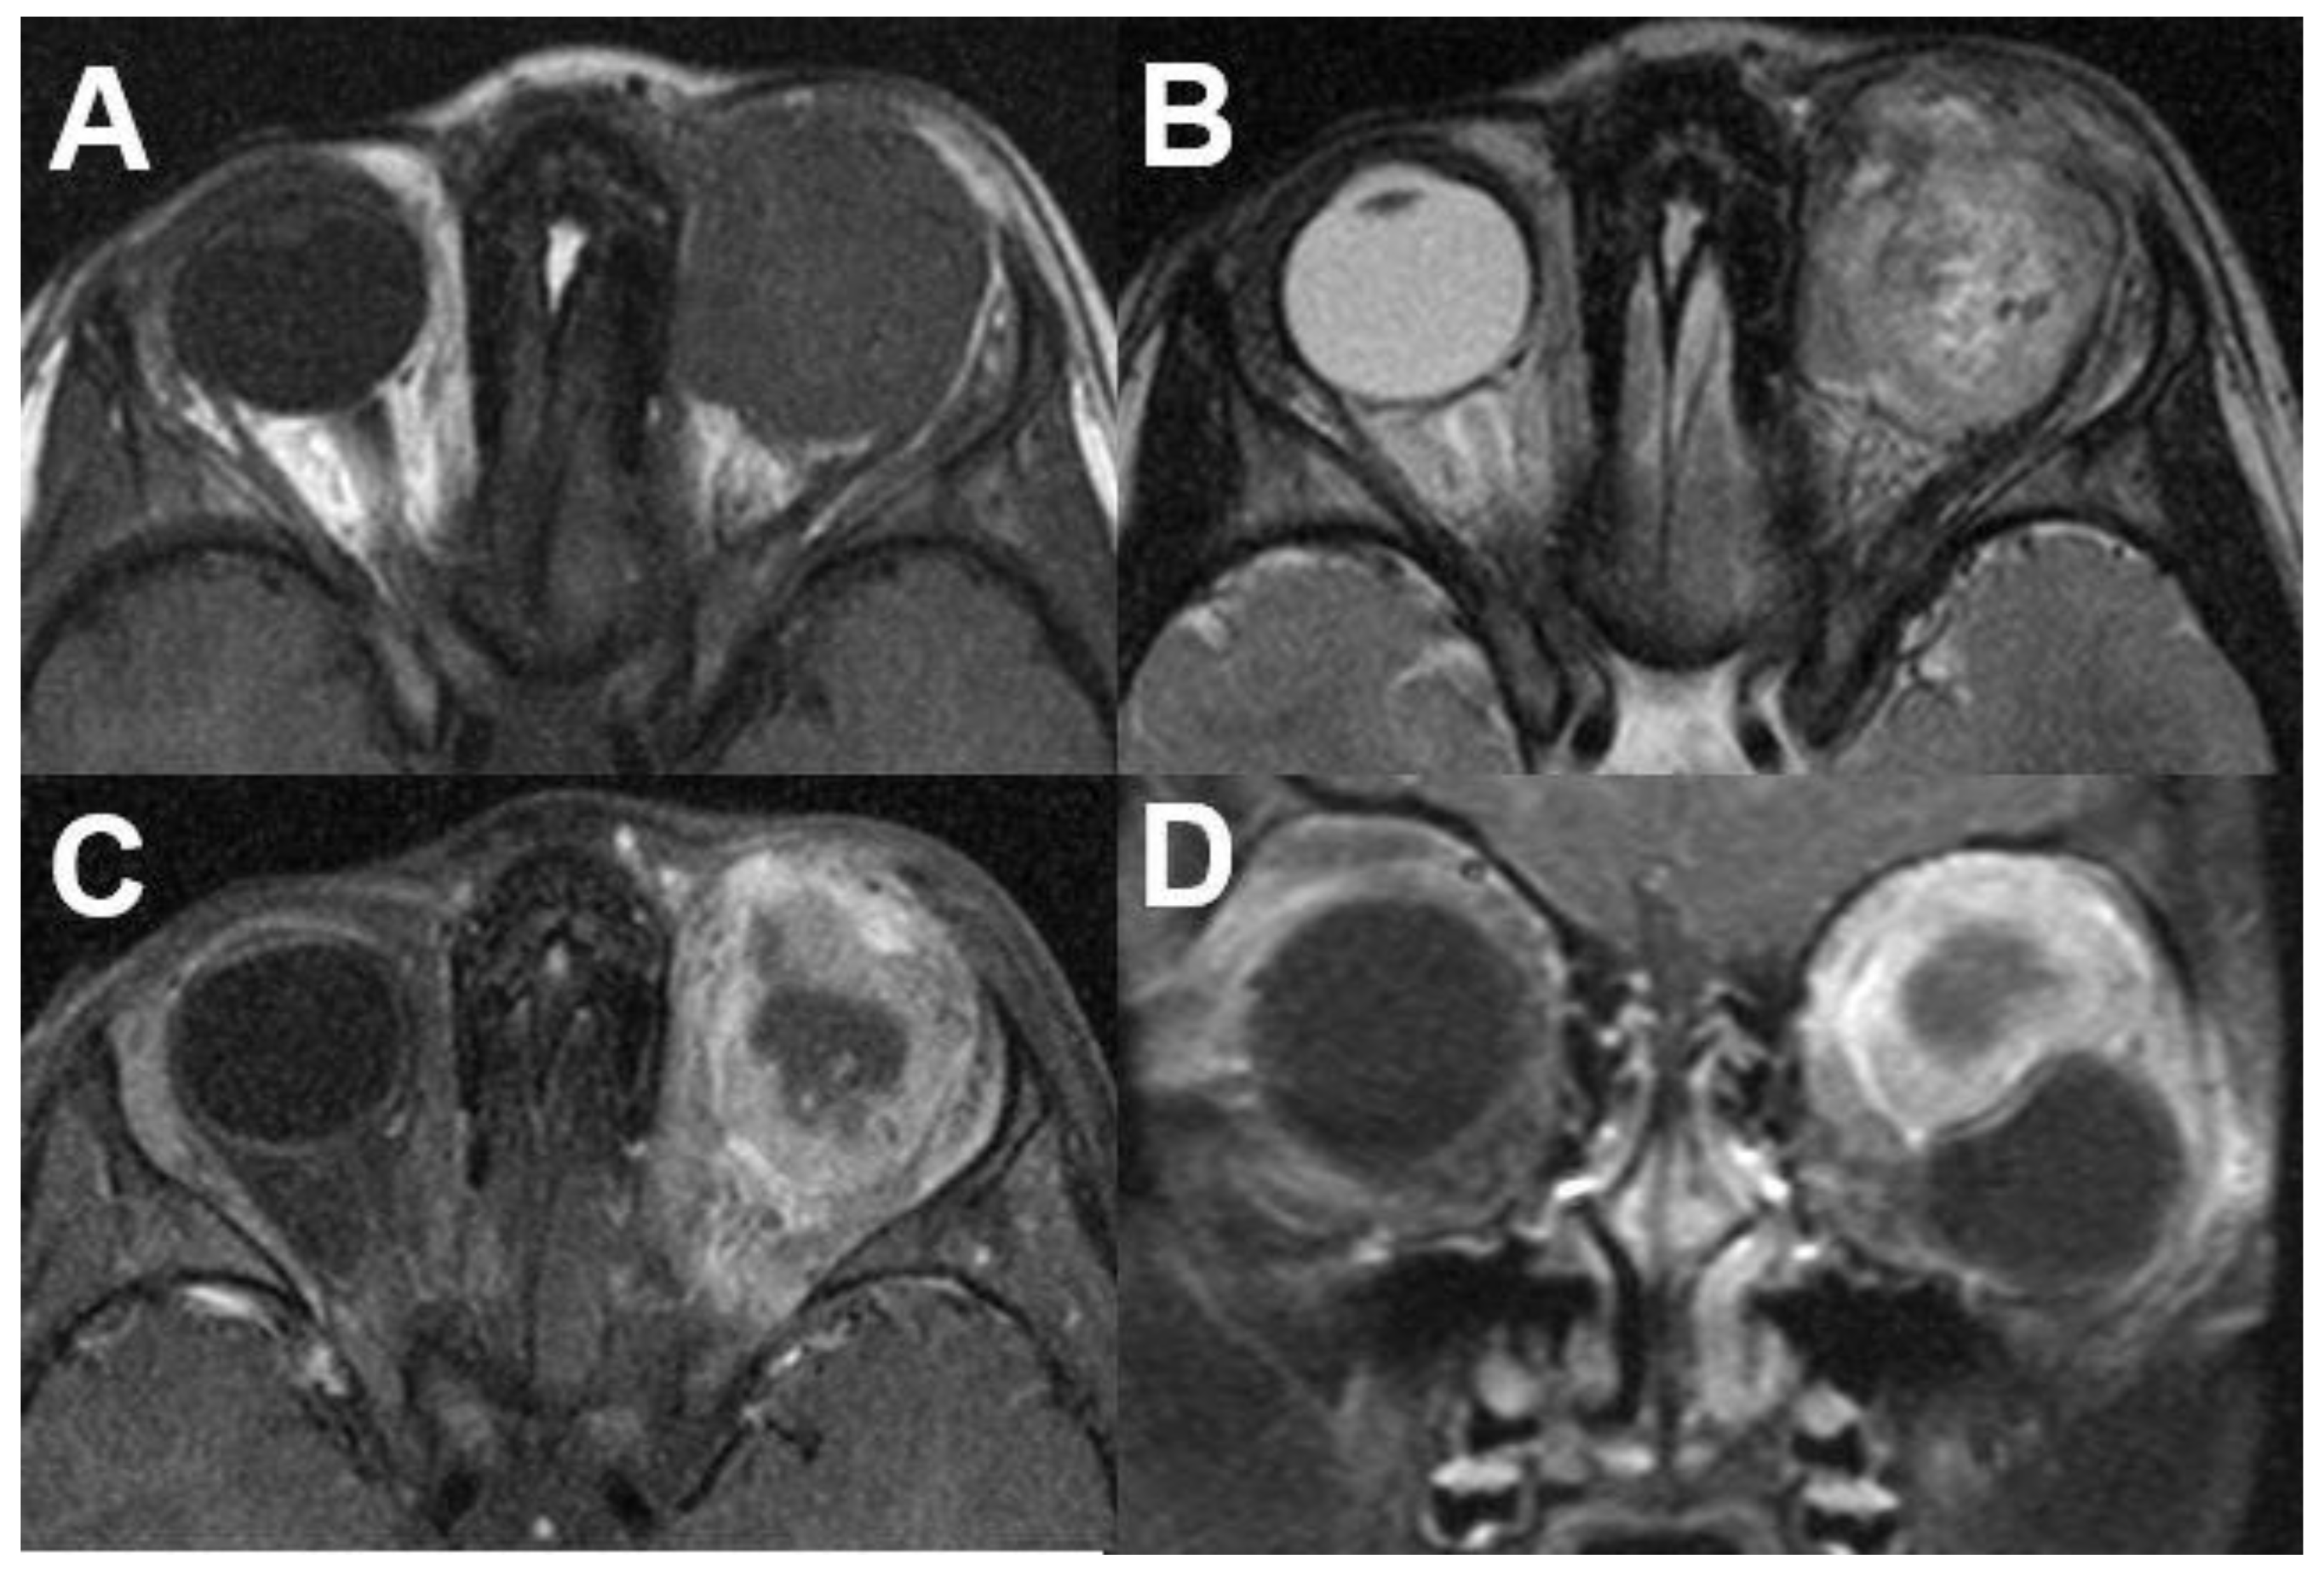

3.1.1. Retinoblastoma

3.1.2. Uveal Melanoma